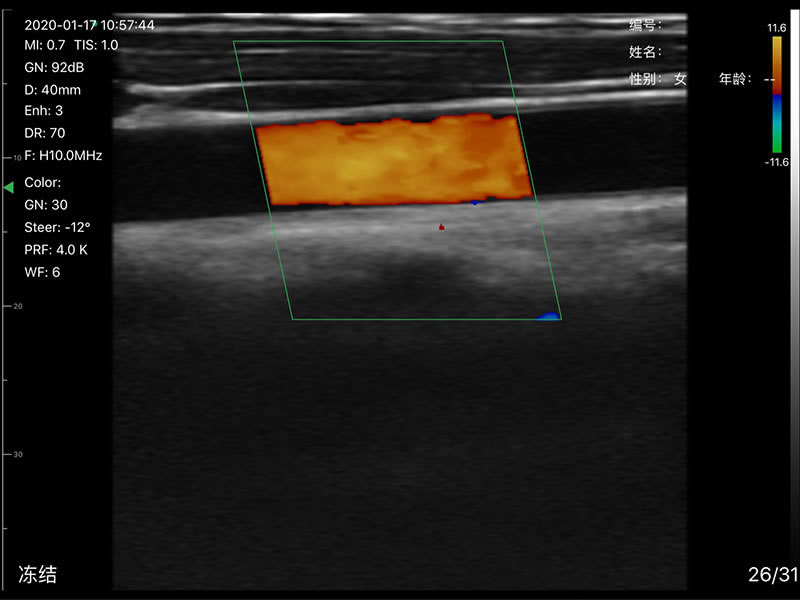

• 显示模式:B、B/M、Color、PW、PDI

• 探头频率:相控阵2.2/3.6MHz,线阵7.5/10 MHz

• 扫描深度:相控阵90-190mm,线阵 20-100mm,可调